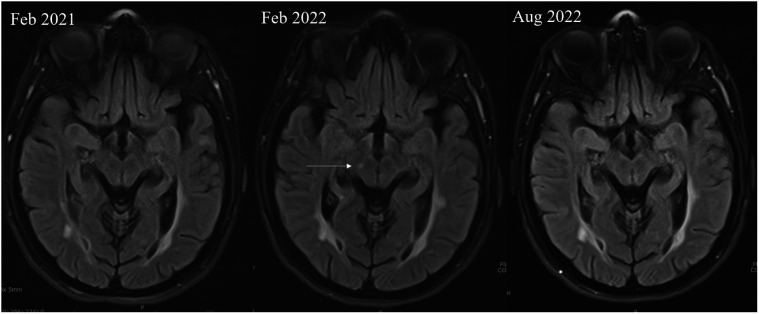

The coexistence of multiple autoimmune diseases in the same individual is unusual and has received little attention in the literature. We present a young female patient with multiple sclerosis, systemic lupus erythematosus, and biopsy-proven renal proteinase 3 antineutrophil cytoplasmic antibodyassociated vasculitis who responded well to intravenous rituximab clinically and serologically.